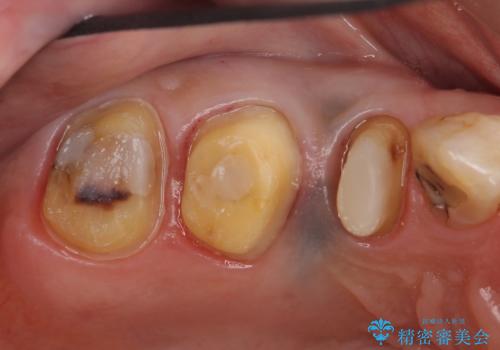

診査の結果痛みの原因は右上7番目だったため、古い樹脂と虫歯を除去後、オールセラミッククラウンによる補綴を行いました。

また右上5、6番目の歯も治療を希望されたため、オールセラミッククラウンによる補綴を行いました。

- オールセラミッククラウン…¥100,000×3、仮歯…¥10,000×3、ファイバーコア…¥20,000費用は治療当時の料金となります